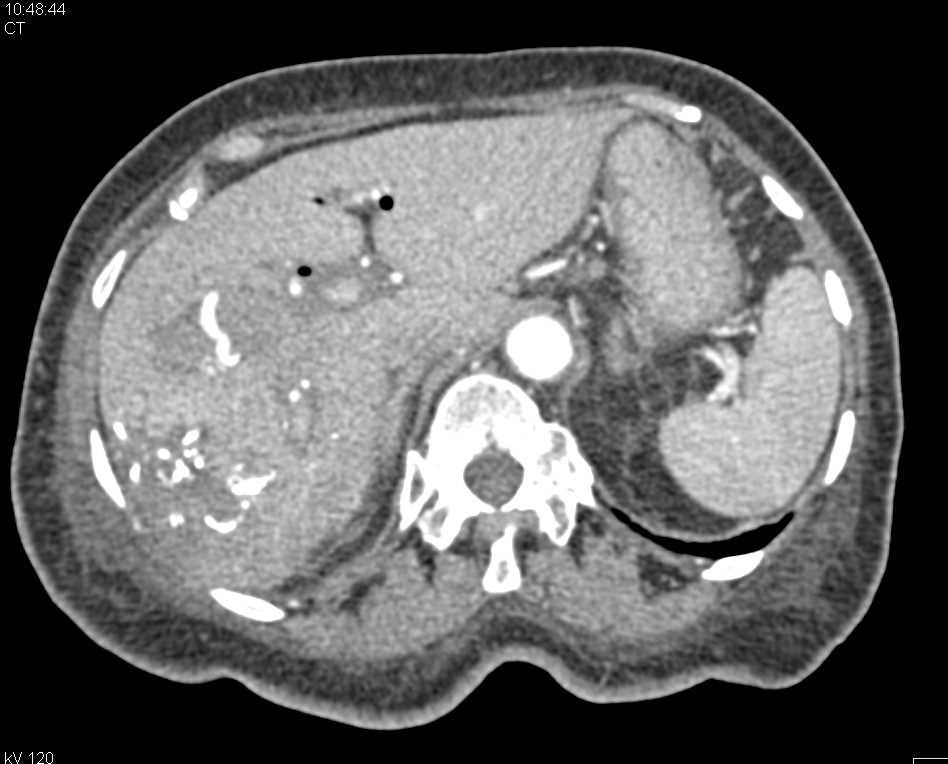

Fibrolamellar Hepatoma